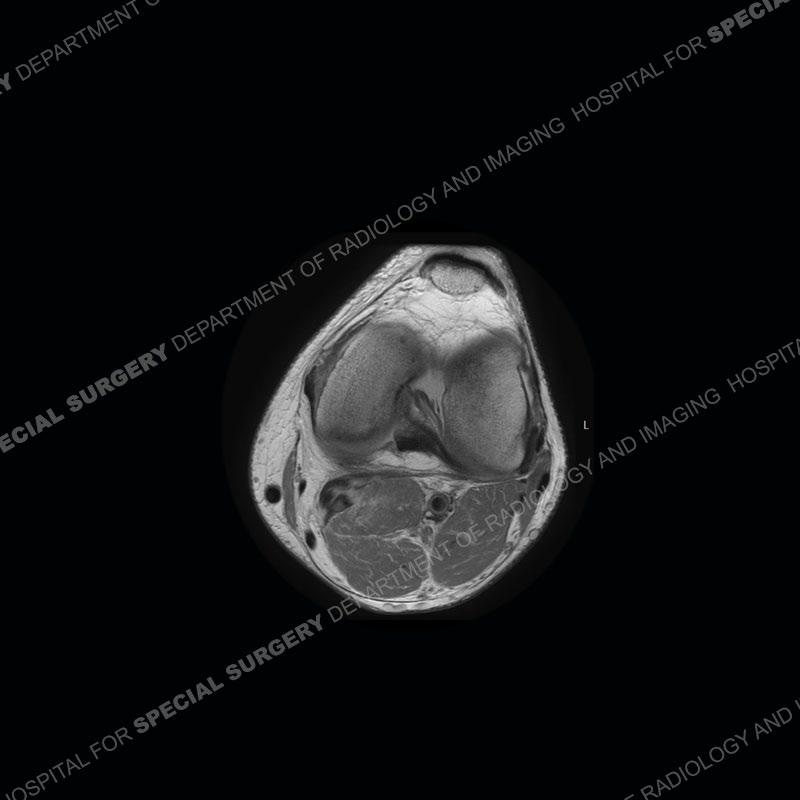

The radiographs show degenerative change of the medial compartment and a varus knee, but they are not germane to this case. No acute bony injury is present. The MRI shows edema of the posterior medial knee/soft tissue and a focal area of a partially disrupted low signal structure. The details are kept at a minimum in the findings of this case on purpose.

Diagnosis: Partial Disruption Medial Head Gastrocnemius (MHG)

The findings were kept purposefully vague as identifying the structures early on takes away a lot of the diagnosis. An uncommon entity and one of which we do not see a lot. Enthesopathic changes and tendinosis are seen as are distal MHG injuries, but proximal tears are rarely present. This case highlights a number of points. One, it almost always comes down to anatomy. Perhaps not a structure we normally spend too much time on, except save for diagnosing a Baker’s cyst, but knowing where this structure and all structures exist in all three planes is imperative. Second, when you think you are making a “call” or finding that you have never made before, step back and think is this just the abnormal presentation of a common pathology. That situation arises much more frequently. Third, if you look at it once, twice, and probably a third time and are confident in your odd or very rare diagnosis, stick to your guns. Especially, when it comes down to anatomic structures, the proof will be in the images.

Fourth, use all imaging planes and different pulse sequences to make your diagnosis. The edema highlighted in this case can be seen as the obscuration of fat on the PD images but is much easier to perceive as the high signal on the IR pulse sequences. The actual disruption of the MHG myotendinous junction is only able to be seen on the axial images. On the sagittal and coronal images, we get a sense something is wrong but hard to be exact. Lastly, when you look at a study and something just seems off (as I would say the sagittal and coronal images do with that dark band of tissue posteriorly), listen to yourself and go through the study slowly and meticulously. Most of the time you will find you were right, and something indeed is present.